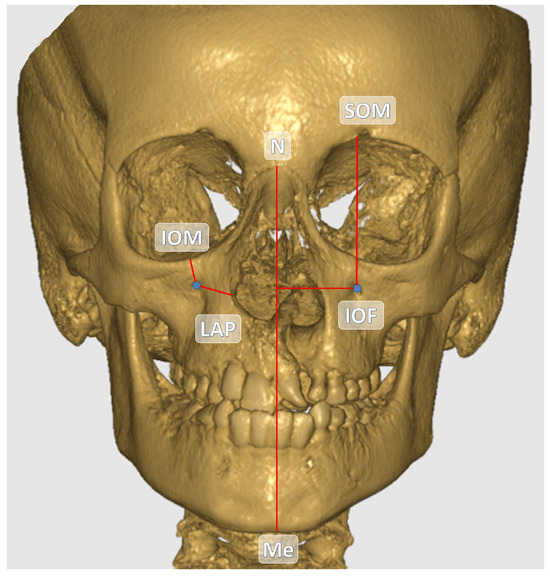

The central point of the infraorbital foramen (IOF) was used as the reference in all measurements. The anatomical landmarks used as references in the study are detailed in Table 1. All measurements were performed in millimeters (mm) based on CBCT images. The distances between the reference anatomical landmarks and the IOF are illustrated in Figure 1 and Figure 2. Additionally, the soft tissue thickness (STT) on the buccal side of the IOF was assessed using sagittal CBCT sections (Figure 3).

Figure 1. Coronal view of the IOF and other anatomical structures on the reconstructed CBCT image.

Figure 2. Sagittal view of the IOF and other anatomical structures on the reconstructed CBCT image.